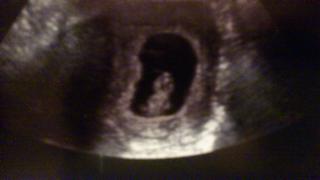

@spula22 ahojte maminky , takto pekne si ja hoviem v brusku som spokojneeeeee

maminka ma tusaka ze asi budem dievcatko , zodpovedame 8 tt podla velkosti 😵 😵 😵 a maminka si poplakala stastim

a mame 15,8 mm 😵 😵